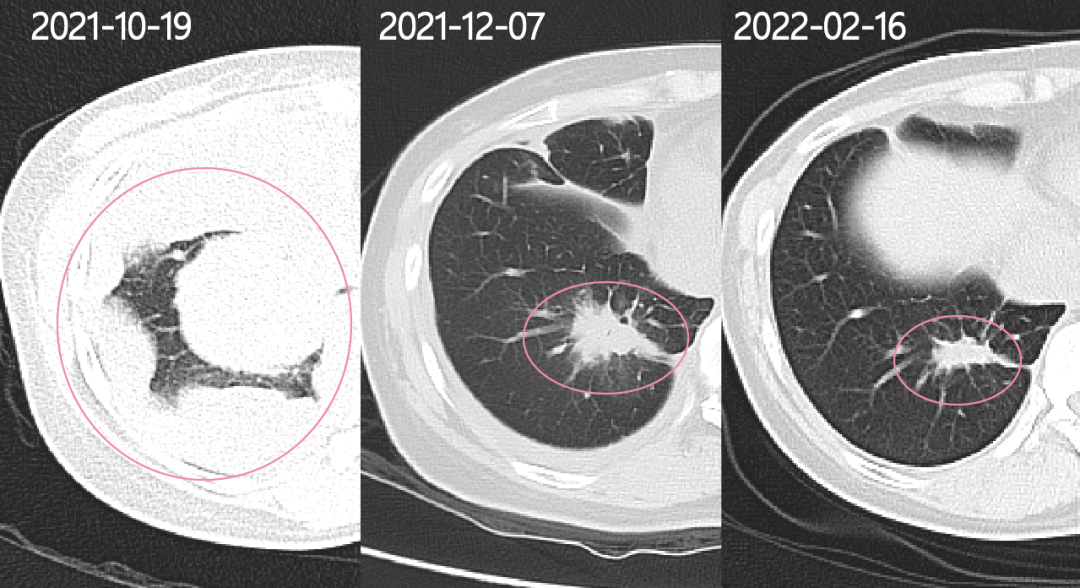

回看老婆每次复查的影像报告,一开始那个5厘米大的肿瘤和一些小瘤子,就像包子一样,鼓鼓囊囊地塞在了老婆的右侧胸腔中,但经过有效治疗后,现在看上去只剩1粒花生米大小了,影像上看胸壁也已经光滑圆润。

5.48CM*5.4CM(确诊时):1.8CM*1.8CM(奥希替尼35天);1.4CM*0.9CM(奥希替尼108天)

2021年12月7日复查

抽了5管子血,但幸运的是带给了我们惊喜!老婆肺部内大的肿物5.48CM*5.4CM缩小到1.8CM*1.8CM,小的病灶开始消失,血液指标也基本正常。

2022年2月17日复查

影像上一切都很好,之前的积液已经全部吸收,整个胸壁轮廓清晰,能看到的只剩下一个肺部病灶,对比了初诊影像(右肺及右胸膜多发恶性占位肺部原发肿瘤5.48CM*5.4CM)和去年12月7日影像(右肺及右胸膜少许结节影原发肿瘤1.8CM*1.8CM),说我们疗效非常好叫我们放宽心不用去担心,即使进展了他们也会有很多办法去应对。